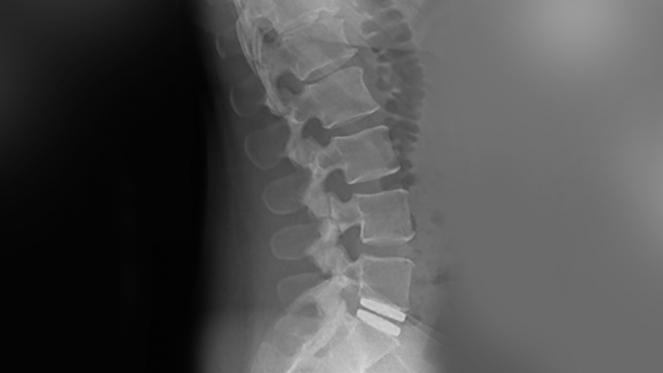

Die Implantation einer Bandscheibenprothese wurde als Alternative zur Wirbelsäulenversteifung entwickelt. Nach Entfernung der beschädigten Bandscheibe, wird eine Bandscheibenprothese eingesetzt. Diese stellt den richtigen Abstand zwischen den Wirbeln wieder her und hält gleichzeitig die Bewegungsmöglichkeiten einer gesunden Bandscheibe aufrecht. Durch die Beweglichkeit kann eine Degeneration der benachbarten Bereiche vermieden werden.

Die lumbale Bandscheibenprothese M6-L stellt aufgrund ihres einzigartigen Designs, welches auf den Eigenschaften einer natürlichen Bandscheibe basiert, eine innovative Option gegenüber anderen lumbalen Bandscheibenprothesen dar. Die M6-L besteht aus einem künstlichen Nukleus (aus Polyurethan) und einen gewebten Faserring (aus Polyethylen). Der künstliche Nukleus und Ring der M6-L besitzen dieselben Bewegungsmerkmale wie eine natürliche Bandscheibe. Umfassende biomechanische Tests haben ergeben, dass die Bandscheibenprothese M6-L gegenüber einer gesunden Bandscheibe eine vergleichbare Bewegungsqualität besitzt. Zusammen bieten der künstliche Nukleus und Ring der M6-L Kompressionseigenschaften sowie einen kontrollierten natürlichen Bewegungsfreiraum. Diese „natürliche“ Bewegung gibt die Freiheit, den Rücken naturgetreu zu bewegen, während die Belastung für benachbarte Bandscheiben und andere wichtige Wirbelsäulengelenke minimiert und eine zusätzliche Degeneration benachbarter Bereiche möglicherweise verhindert oder verzögert wird.